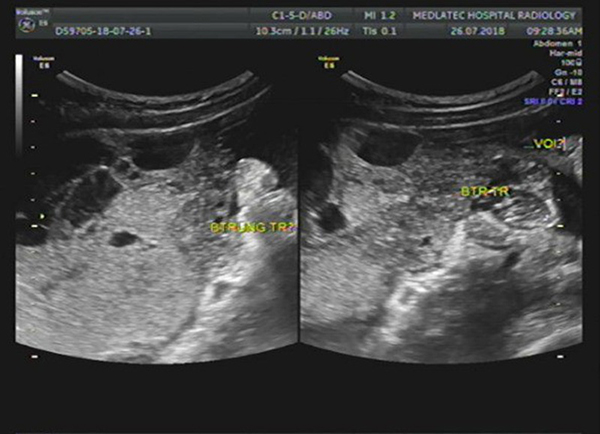

Siêu âm có phát hiện U nang buồng trứng không?

Vì lo sợ bản thân bị U nang buồng trứng, nhưng lại không an tâm vì không biết siêu âm có phát hiện U nang buồng trứng hay không? Nên đây trở thành vấn đề được nhiều chị em tìm hiểu. Vậy rốt cuộc siêu âm có phát hiện U nang buồng trứng không? Cùng đọc tiếp ngay bạn nhé.

Siêu âm có phát hiện U nang buồng trứng không?

Hiện nay, siêu âm là cách thức nhanh và tốt nhất để phát hiện U nang buồng trứng. Do đó, nếu bạn muốn kiểm tra buồng trứng của mình, đừng băn khoăn liệu: siêu âm có phát hiện được U nang buồng trứng hay không. Vì chắc chắn 100% là có.

Với máy móc tiên tiến và hiện đại. Các đời máy siêu âm hiện nay có thể phát hiện được U nang trong giai đoạn sớm. Từ đó, giúp bệnh nhân có được các phương án theo dõi khám bệnh và điều trị kịp thời. U nang buồng trứng có thể chữa khỏi, tuy nhiên nếu để kéo dài không phát hiện, có thể gây ra biến chứng nguy hiểm.

Siêu âm có phát hiện U nang buồng trứng, nhưng để nắm rõ nhất tình trạng bệnh của mình, bạn nên chọn cơ sở khám bệnh uy tín. Một bác sĩ giàu kinh nghiệm mới có thể đọc kết quả siêu âm chính xác nhất và đưa ra phương án điều trị U nang buồng trứng tốt nhất.

- Siêu âm: cách thức để phát hiện xem bệnh nhân có bị U nang buồng trứng không